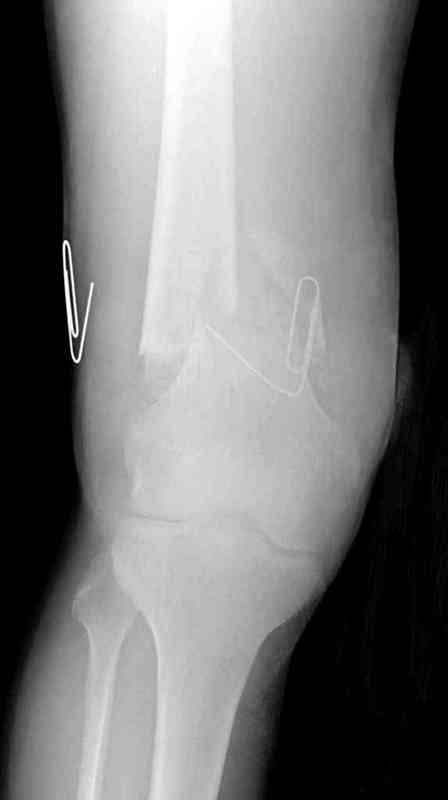

Укороченный фрагмент с самого начала являлся проблемным, на рентгене не видны следы от множественных спиц, обычно применяемых для лечения "коротких" переломов.

Адекватную фиксацию можно получить путем экстрафокальной косой остеотомии более проксимально, тем самым удлинить дистальный фрагмент, без повторной работы в фокусе патологии, что, в свою очередь, приведет к еще большему укорочению фрагмента.

Как предлагают коллеги, свежие стрессовые снимки уточнят наличие подвижности, а длинный на всю длину конечности снимок позволит провести точный предоперационный расчет по коррекции.

Предпочтительно фиксацию провести пластинами, во-первых, можно было сделать квадрицепс-пластику по Judet для восстановления движения в суставе, а потом коррекцию и фиксацию кондилярной пластиной с угловой стабильностью. Стерильный турникет на конечность поможет уменьшить кровепотерю во время операции.